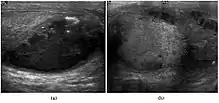

Fig. 3. Seminoma. (a) Seminoma usually presents as a homogeneous hypoechoic nodule confined within the tunica albuginea. (b) Sonography shows a large heterogeneous mass occupying nearly the whole testis but still confined within the tunica albuginea, it is rare for seminoma to invade to peritesticular structures.

Approximately 95% of malignant testicular tumors are germ cell tumors, of which seminoma is the most common. It accounts for 35%–50% of all germ cell tumors. Seminomas occur in a slightly older age group when compared with other nonseminomatous tumor, with a peak incidence in the fourth and fifth decades. They are less aggressive than other testicular tumors and usually confined within the tunica albuginea at presentation. Seminomas are associated with the best prognosis of the germ cell tumors because of their high sensitivity to radiation and chemotherapy.

Seminoma is the most common tumor type in cryptorchid testes. The risk of developing a seminoma is increased in patients with cryptorchidism, even after orchiopexy. There is an increased incidence of malignancy developing in the contralateral testis too, hence sonography is sometimes used to screen for an occult tumor in the remaining testis. On US images, seminomas are generally uniformly hypoechoic, larger tumors may be more heterogeneous [Fig. 3]. Seminomas are usually confined by the tunica albuginea and rarely extend to peritesticular structures. Lymphatic spread to retroperitoneal lymph nodes and hematogenous metastases to lung, brain, or both are evident in about 25% of patients at the time of presentation.